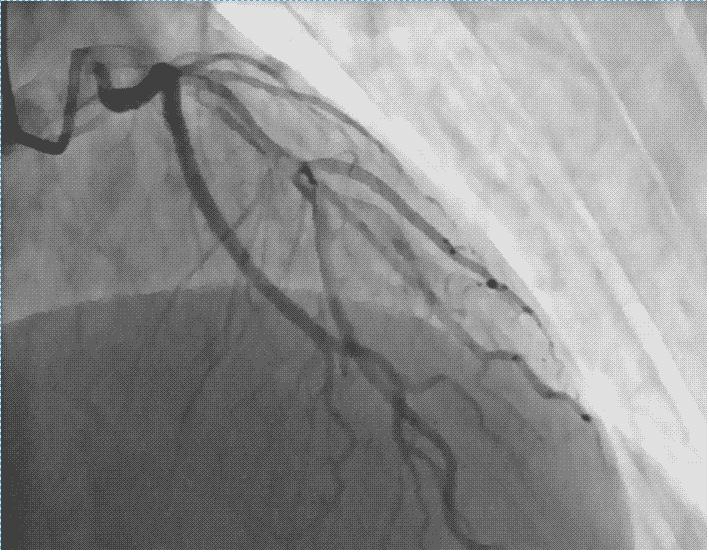

在上面的步骤完成后,我们就有一个鞘管留在手臂上了,这个时候就可以沿着鞘管把造影导管沿着动脉往上送,一直送到心脏冠状动脉开口的地方,注射造影剂就可以让心脏血管显示出来,哪里有狭窄,狭窄有多重?都一清二楚了!这个过程由于血管里没有神经,一般人是没有明显感觉的,当然也不会疼。